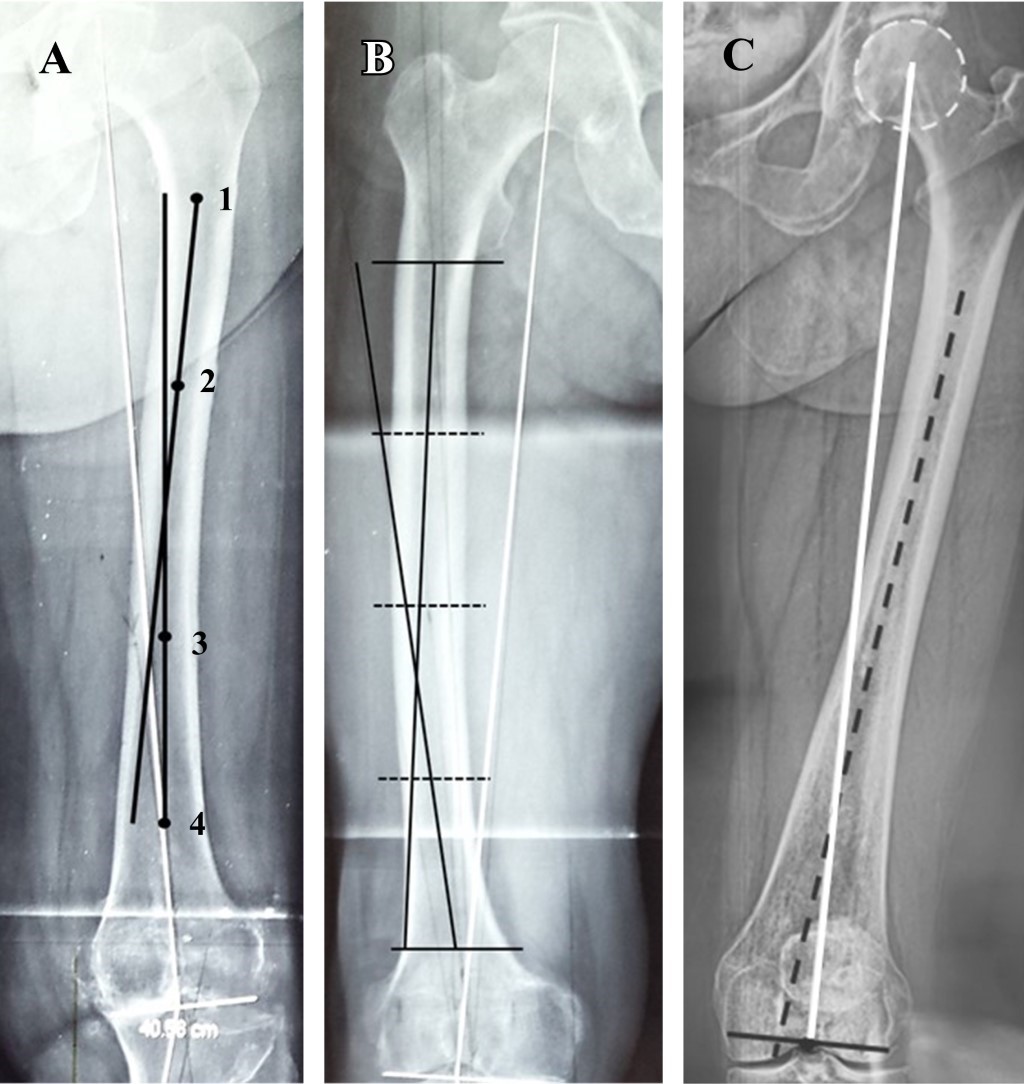

La necesidad de artroplastia total de rodilla está aumentando considerablemente y uno de los objetivos es lograr la alineación coronal postquirúrgica. La asistencia quirúrgica robótica consigue una alineación funcional, que es un ángulo cadera-rodilla-tobillo de 0°. Sin embargo, no es posible ofrecer cirugía asistida por robot a todos nuestros pacientes, por lo que debemos incluir la radiografía AP de soporte de peso de cadera a tobillo de cuerpo entero en la planificación preoperatoria para obtener una alineación de "zona segura", que es un ángulo postquirúrgico cadera-rodilla-tobillo de 0 ± 3°. ¿Cómo podemos conseguir una artroplastia total de rodilla con alineación de "zona segura" en pacientes con deformidad extraarticular?

Figura 3